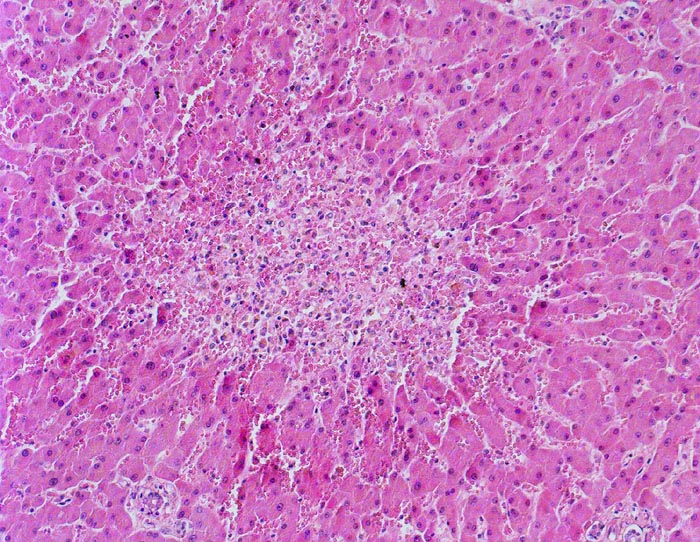

Zonale perizentrale Parenchymnekrose bei Schock

vaskulär / Durchblutungsstörung

Leber

Im Bildzentrum die Zone 3. Ein Zentralvenenlumen ist nicht erkennbar. Anstelle von regelrecht aufgebautem Parenchym ist eine blutdurchtränkte Zone mit Entzündungszellen anstelle von Hepatozyten getreten. Die Sinusoide der Zone 2 zeigen eine Blutstase.

Schweres akutes Rechtsherzversagen bei multiplen zentralen und perizentralen Lungenembolien.